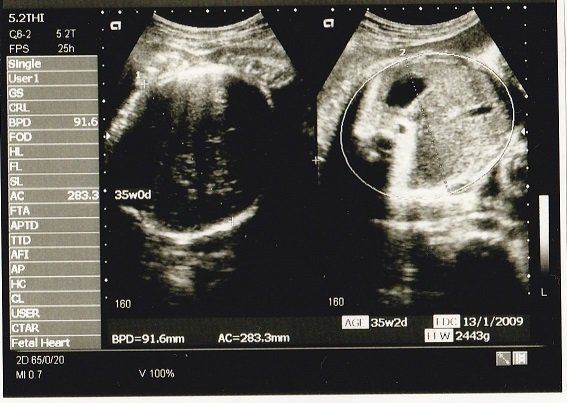

妊娠35週目のエコー写真 いよいよ出産へ

妊娠9カ月になり、いよいよ出産に向けての準備段階です。母親学級に参加して、出産についていろいろと勉強しました。待望のわが子に会えるまで、あと少しです!

私の息子は生まれたときから髪がふさふさでした。このころから髪が伸びていたのかな?

息子は、妊娠38週目に体重2978g、身長50.5㎝で、元気に生まれてきてくれました。